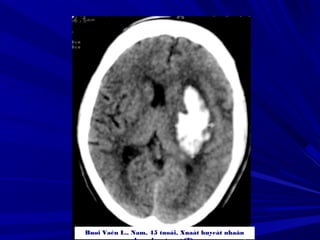

Buøi vaên L., Nam, 45 tuoåi, Xuaát huyeát nhaân beøo-bao trong (P) coù

traøn maùu naõo thaát

Buøi Vaên L., Nam, 45 tuoåi, Xuaát huyeát nhaân